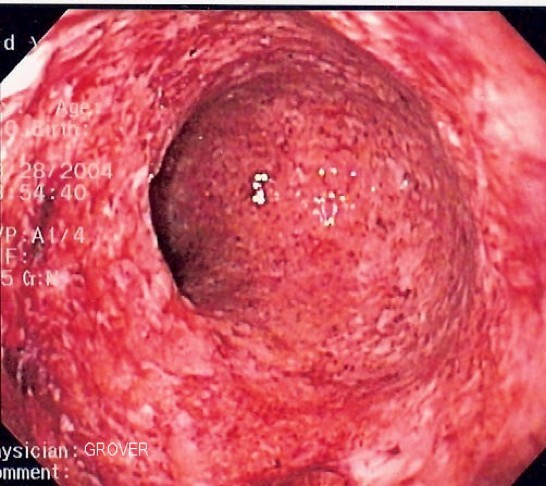

A 55 year old obese man reports frequent chest pain, especially after eating spicy foods or drinking coffee. What is his diagnosis based on the endoscopic exam and what are the complications of this condition?

GERD: see hyperemia, vertical linear streaks due to mucosal erosions/ulcers

Associated symptoms: Regurgitation, pulmonary symptoms (adult-onset asthma), cough (at night), hoarseness, laryngitis, chest pain, disturbed sleep

1) 24-hour ambulatory esophageal pH monitoring= gold standard (measures proximal and distal esophagus, stomach pH)

2) Endoscopy (with biopsy)- rule out other pathology, look for Barrett’s

3) Bernstein test= reproduce patient’s symptoms by infusing acid into esophagus

Complications: Esophagitis–> peptic stricture, esophageal hemorrhage, ulcer, pulmonary symptoms, Barrett’s esophagus